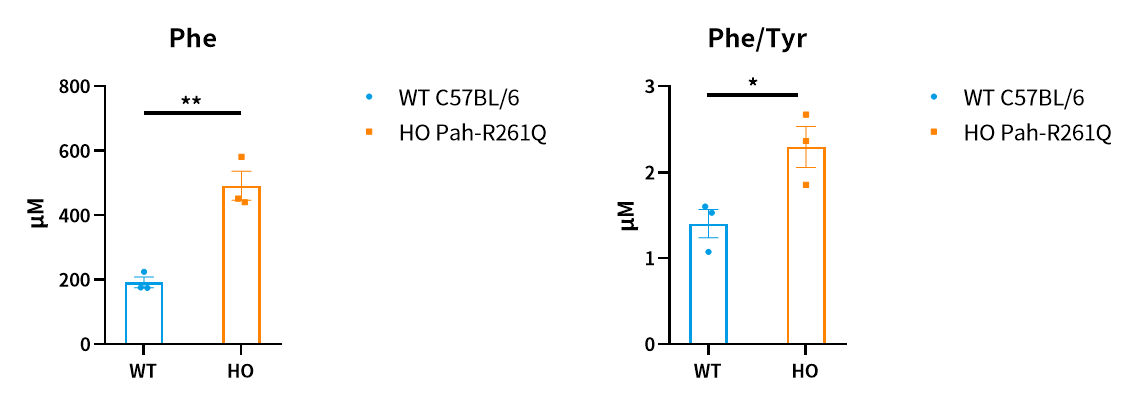

Fig4. Detection of blood serum concentrations of the metabolites in Pah-R261Q mice by LC-MS